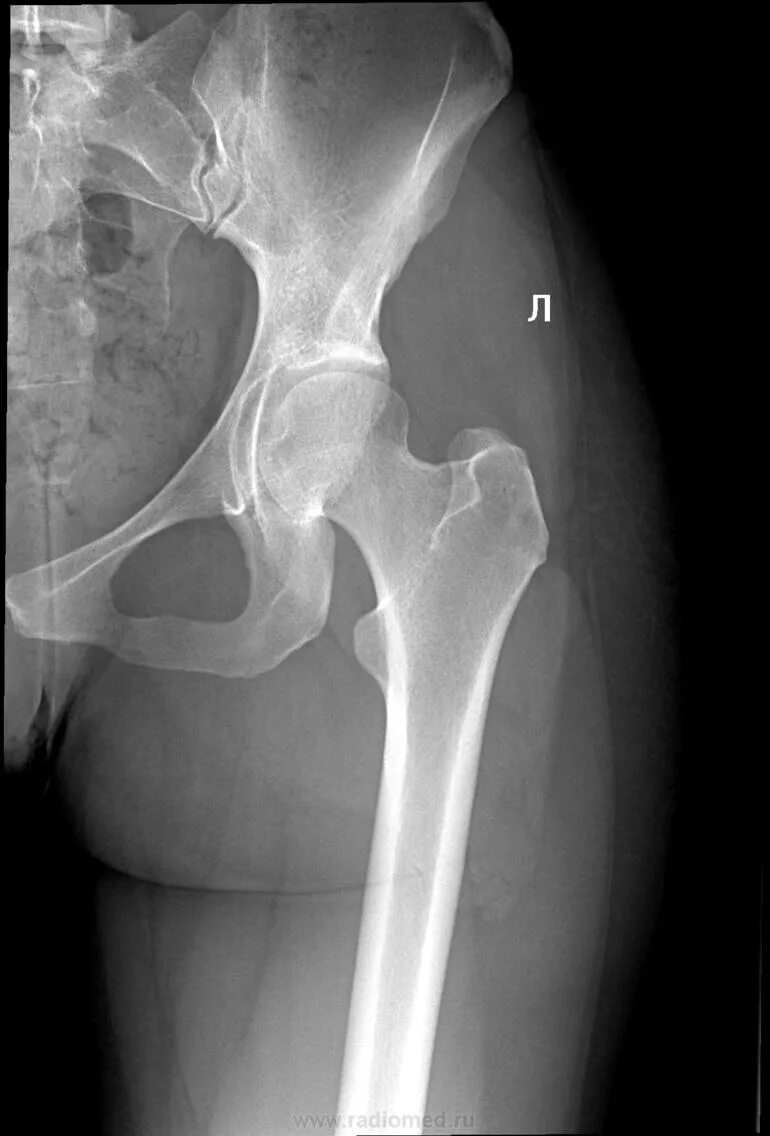

Тазобедренный сустав 3 степени лечение